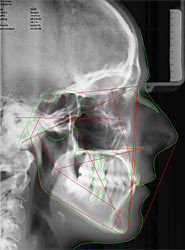

- Röntgenaufnahme des Kopfes von der Seite

Wie sind die Lagen des Oberkiefers und des Unterkiefers?

Wie ist die Neigung der vorderen Zähne im Ober-, und Unterkiefer?